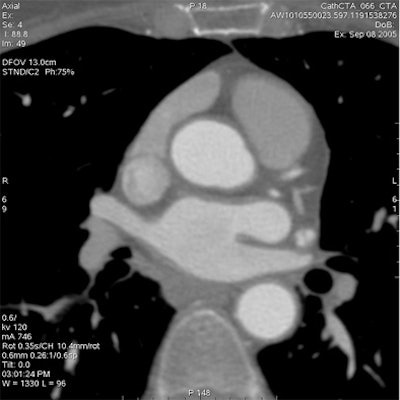

Which image would you rather be responsible for? Small 13-cm FOV (above) provides the best cardiac image quality at the lowest radiation dose compared with medium 25-cm FOV coronary CTA image (below). Thoracic image (bottom) maximizes anatomic coverage but at the cost of additional radiation and potentially more incidental findings. All images courtesy of Dr. Matthew Budoff.

The heart fits in a 25-cm field-of-view, permitting the use of a small bowtie filter in medium-sized and sometimes even larger patients, Budoff said. "We're only worried about the heart," he said.

For example, using protocol parameters of 600 mA, 120 kV, and a heart rate of 60 bpm, a small cardiac bowtie filter (standard 25-cm FOV) permits cardiac images to be acquired at dose-length product (DLP) of 474 (8.0 mSv), Budoff said. A medium bowtie filter (allowing reconstruction to 36-cm FOV) affords a dose of 791.4 DLP (13.4 mSv).

For most patients, following the principles of ALARA (dose as low as reasonably achievable), confining the field-of-view, and using a small bowtie filter for all patients undergoing cardiac scanning has the best resolution and evidence of efficacy, Budoff said.